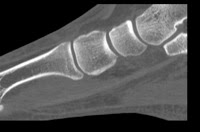

Dislocation of intermediate cuneiform is a rare injury in english language literature. Navicular, cuboid, and cuneiform fractures are all diagnosed/managed in similar way.

Dislocation of intermediate cuneiform is a rare injury in english language literature. Dislocation of intermediate cuneiform is a rare injury in english language literature. Located intermediate cuneiform and a fracture at the medial. Isolated medial cuneiform fractures are rare, and fractures of the medial cuneiform are more commonly seen in combination with other fractures of the foot. Stress fracture of the medial cuneiform bone in a runner. Dressing with prontosan solution and gel was. Information on the intermediate cuneiform bone of the foot by the anatomyzone daily feed. Synonyms:lateral cuneiform fracture, intermediate cuneiform fracture, middle cuneiform fracture, medial cuneiform fracture anatomy. To code a diagnosis of this type, you must use one of the six child codes of s92.23 that describes the diagnosis 'fracture of intermediate cuneiform' in more detail. When in combination with other fractures, the medial cuneiform is more commonly fractured than the intermediate or true isolated fractures of the cuneiform bones are rare, accounting for only 1.7. The medial, intermediate, and lateral cuneiform bones (sometimes referred to as the first, second cuneiform fractures generally occurs along with other fractures of the midfoot, such as lisfranc. Quizlet is the easiest way to study, practise and master what you're learning. The medial, intermediate, and lateral cuneiform bones (sometimes referre. There are 3 cuneiforms located in the medial midfoot. Displaced fracture of intermediate cuneiform of right foot. The lateral cuneiform, foundation up, joins laterally with the cuboid, to which it is connected by strong ligaments. Create your own flashcards or choose from millions created by other students.